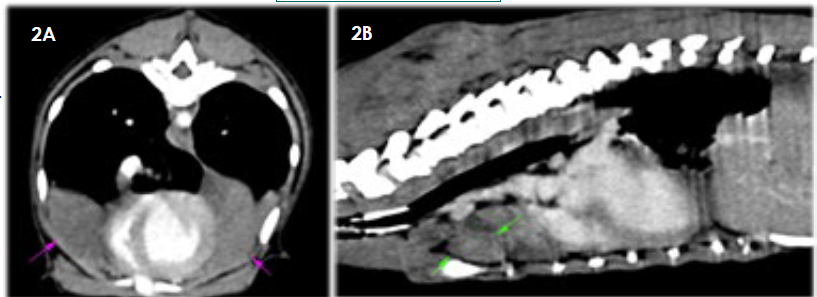

Se describe el caso de un cachorro mestizo, enterode 8 meses que acudió a consulta de urgencias por un cuadro de fiebre y dolor cervical de 7 días de evolución, progresando a disnea marcada secundaria a un hemotórax espontáneo.